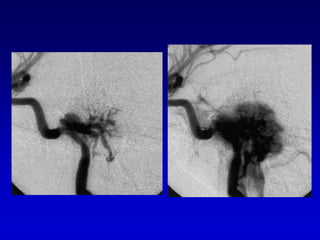

Caso 3TAC RM ANGIO

Caso 3

postembolizacion